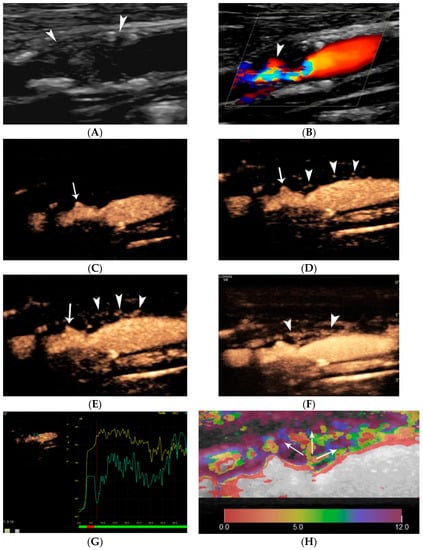

4.1.1. Intraplaque Neovascularization

4.1.4. Plaque Ulceration

4.2. CEUS and Intraplaque Inflammation

4.2.2. PET Imaging

4.3. CEUS and Clinical Events